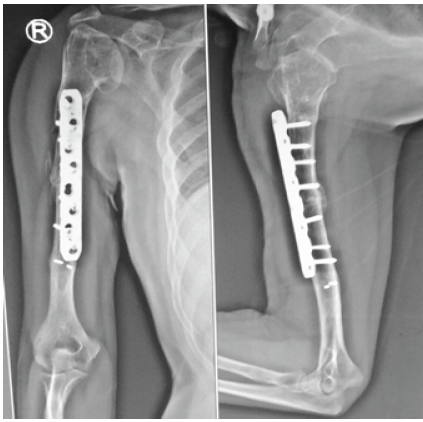

The post-operative course was uneventful. Early shoulder and elbow mobilization was initiated following wound healing. Immediate post-operative radiographs demonstrated stabilization of the right mid-shaft non-union with plate osteosynthesis, adequately bridging the previous fracture site and maintaining satisfactory alignment and length of the humerus (Fig. 5).

Figure 5: Immediate post-operative anteroposterior and lateral radiographs showing stabilization of the right mid-shaft nonunion with plate osteosynthesis, bridging the previous fracture site and maintaining satisfactory alignment and humeral length.